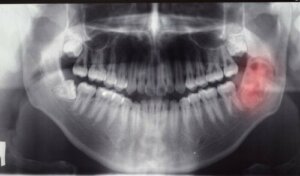

Diagnostyka

Guzy i cysty w jamie ustnej zwykle nie dają objawów i odkrywa się je przypadkowo. Czasami jednak mogą prowadzić do stanów zapalnych, bólu zębów czy opuchlizny dziąseł.

W celu uzyskania pełnego obrazu wykonuje się więc badania RTG i pantomogram.

Co więcej, można przeprowadzić biopsję, w celu sprawdzenia czy zmiana jest złośliwa. Na podstawie tych informacji lekarz decyduje o podjęciu odpowiedniego leczenia.